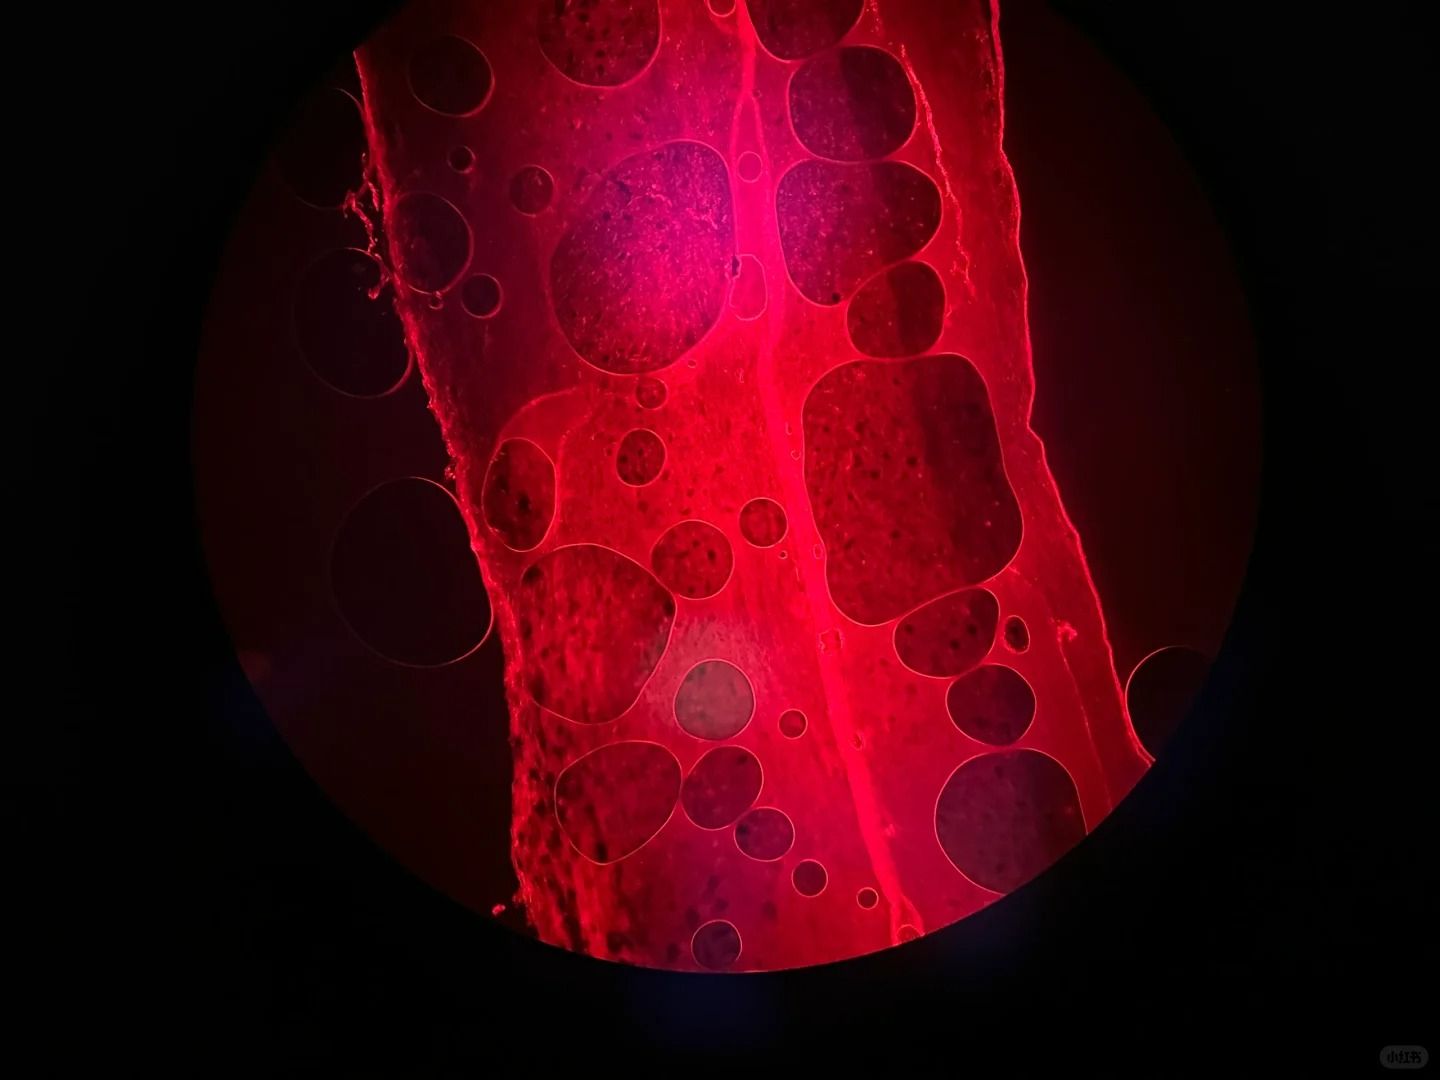

六、切片表面有氣泡

切片表面出現氣泡,可能是組織冷凍時內部含有過多水分或空氣造成的。

為了消除氣泡,我們可以嘗試以下方法:

①在組織冷凍前,用吸水紙輕輕吸去組織表面的多余水分。

②在切片過程中,輕輕按壓切片,幫助排除氣泡。